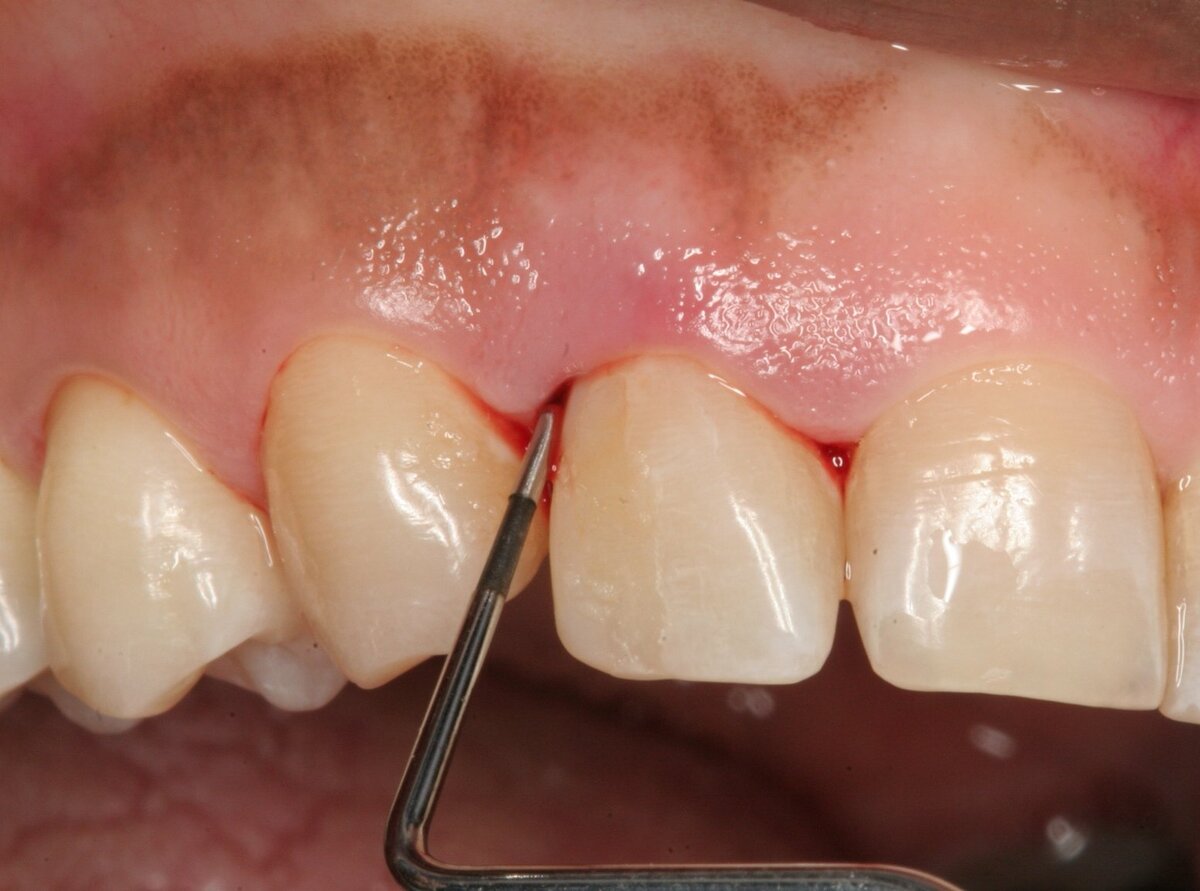

• Развитие воспалительного процесса в ротовой полости. Стоматит, гингивит или пародонтит приводят к нарушению нормальных обменных процессов, что усиливает чувствительность слизистых оболочек и предрасполагает к появлению крови из дёсен при чистке зубов.

• Образование налёта и камня. Появление налёта на зубах происходит вследствие недостаточного ухода за ротовой полостью, при курении и употреблении слишком крепкого чая. Со временем этот налёт минерализуется, становится твёрдым и появляется зубной камень, травмирующий слизистые оболочки рта.

• Неправильную установку ортопедических конструкций. Острые края коронок, протезов и пломб, зазубрины на них повреждают мягкие ткани ротовой полости, нарушая целостность слизистых оболочек дёсен.